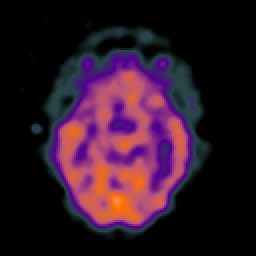

SPECT TC Study #5 -- Slice #23

[Home][Help][Clinical][Tour 1][Tour 2][Tour 3] Slice 23